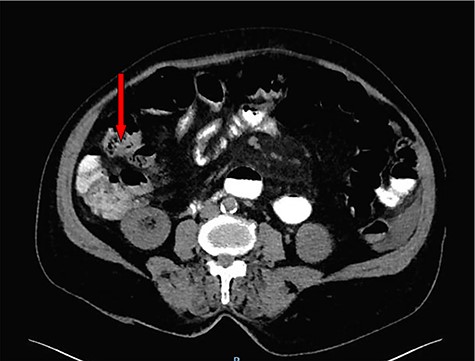

Erect abdominal film demonstrated dilated small bowels alongside the presence of air-fluid filled loops (Fig. 1). Abdominal ultrasound revealed extensively dilated small bowels with multiple gas-filled levels with maximum diameter of 3.5 cm (Fig. 2). Computed tomography (CT) showed the presence of dilated small bowels and local bowel thickening, compatible with the features of small bowel obstruction (Fig. 3). Laboratory data were grossly normal with no evidence of electrolyte abnormalities or increased white blood cell count.

Contrast-enhanced CT scan suggests an appearance of intraluminal debris containing air bubbles ‘mottled appearance’.